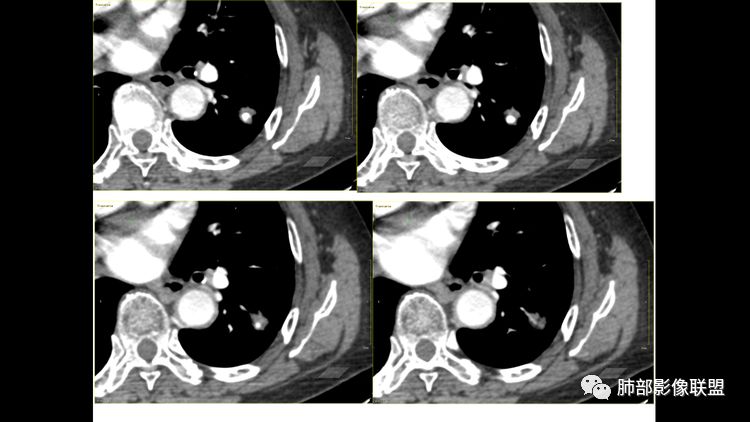

倾向于良性病变,我考虑到的常规疾病谱:PSP,炎性肉芽肿,和错构瘤,AVM。目测强化偏中度强化,结节状致密钙化,病灶内见细支气管通畅显示,考虑PSP大于炎性肉芽肿大于错构瘤。我觉得病灶内的脂肪密度是假象,需要薄层观察。动静脉未见增粗,我觉得AVM可以排除。sun dt:

重点是钙化;是病灶的一部分还是原来的钙化被病灶包埋了冬瓜:支持炎性病变Shelia:这个增强的CT值是多少啊

看了薄层我也倾向于恶性肿瘤。叶间裂牵拉比较明显了,分叶,胸膜凹陷,周围清晰磨玻璃,支气管也闭了。

这属于瘢痕癌,有炎性特点,有长索条影,有钙化,血管进入,比较自如,边缘似乎有点毛糙,有长索条影,有恶性特点,大家都关注钙化了,关注边缘收缩了,

南边:首先,他有炎性的特点,有长索条吧,还有一个大的钙化。对不对,血管进去里面走行也自如,边缘似乎有点毛糙,但是没有薄层,不是很好看。

南边:它符合一个纤维索条影的一些病变存在的特点,为什么,有长索条边缘是吧,近端也是。

南边:但是它也有很多恶性的特点,大家没注意而已,大家把精力所有的关注在哪里?关注钙化灶里面去了,关注在纵隔窗的一个边缘收缩去了。